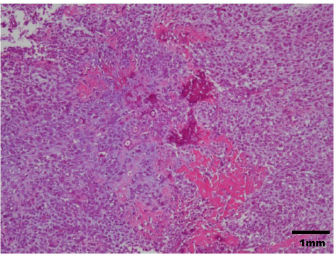

Fig. 4. Histopathological diagnosis was OSA.

A 14-year-old spayed female Labrador retriever weighing 21.3 kg was referred to our hospital with a main complaint of chronic right-hind lameness. This patient had undergone surgery for right tibial fracture repair with implantation of bone plate and screws at a referral hospital 12 years ago. The patient showed no appetite, was not drinking, and was lethargic, with a body condition score of 1/5. The patient was unable to stand up on her own, her right hind limb was mostly weak, and she was unable to move independently using her left side. The patient’s state of consciousness was normal. On physical examination, her vital signs were normal (temperature: 38.1°C, pulse 104 beats/minutes with no heart murmur, respiratory rate with normal lung sounds: 32 beats/minutes). The mucous membrane showed a pale color because of severe anemia (packed cell volume 20.4%). In addition, the capillary refill time was delayed by <3 seconds, suggesting severe dehydration. The patient showed swelling and was warm to the touch from the right tibia to the femur, with a swollen right popliteal lymph node, which presented with a ruptured mass lesion approximately 7 × 10 cm in size. The thoracic radiograph was normal (Fig. 1). However, the right hind limb radiograph showed an osteolytic lesion accompanying the ruptured implant and loosening of the plate and screws, with surrounding soft tissue swelling (Fig. 2). Fine needle aspiration from this site suggested OSA (data not shown). Although we could not perform angiographic computed tomography because of the owner’s dissent, we performed amputation from the hip joint on the same day. Gross morphology showed severe inflammation surrounding soft tissues, the rupture of the stainless-steel bone plate, and we noted a non-medical band at the right tibia (Fig. 3). The patient was formally diagnosed with OSA after histopathological examinations (Fig. 4). After 24 hours hospitalization, we administered ampicillin potassium (20 mg/kg, BID) intravenously and prednisolone (0.5 mg/kg, SID) subcutaneously for postoperative care. Also, 24 hours continuous rate infusion of fentanyl (5 μg/kg/minutes) in lactated Ringer’s solution was used for analgesia. The patient was discharged to the owner the day after surgery for home care. The owner refused postoperative radiation therapy and chemotherapy. Unfortunately, this patient died 1 month after amputation.